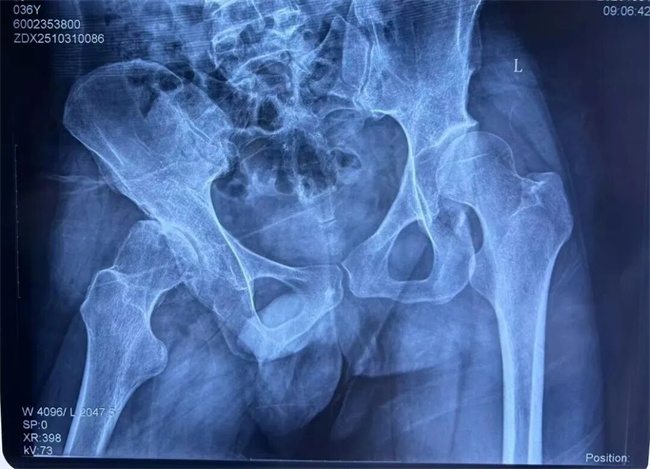

一、患者张某某,男,44岁,患者腰部及右髋部疼痛半月余,弯腰时、久卧后、久坐及劳累后症状加重,活动受限。为求进一步治疗,来到我院请专家会诊,通过各位专家会诊查体、查看影像资料并细致认真的分析后,意见:建议微创手术治疗。

三、患者张某某,男,36岁,患者右髋部疼痛4年,加重1个月,外展活动受限。为求进一步治疗,来到我院请专家会诊,通过各位专家会诊查体、查看影像资料并细致认真的分析后,意见:住院治疗(右髋臼发育不良继发髋关节炎)。